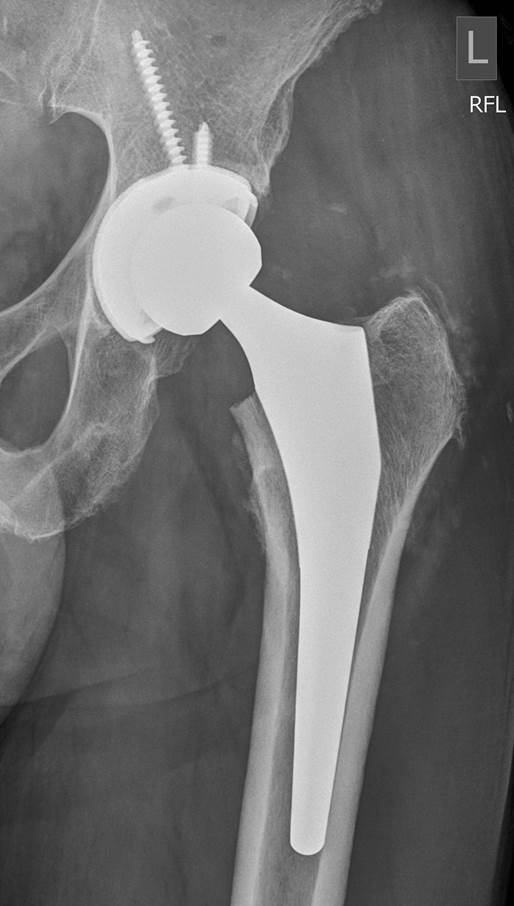

TOTAL HIP REPLACEMENTS Dr Andre Olivier Orthopaedic Surgeon Are There Any Recalls On Hip Replacements However, as with any type of surgery there are risks. Your doctor will explain these to. The aaos device recall dashboard provides orthopaedic surgeons with timely recall information that will protect the health and well. Stryker voluntarily recalled all of its rejuvenate and abg ii hip replacements from the market in july 2012. A hip replacement is a common and. Are There Any Recalls On Hip Replacements.

Illustration of typical hip replacement components Hip and Knee Are There Any Recalls On Hip Replacements The fda is getting the word out regarding a recall effort from zimmer biomet, related to its discontinued cpt hip implant and. However, as with any type of surgery there are risks. The aaos device recall dashboard provides orthopaedic surgeons with timely recall information that will protect the health and well. The potential for fretting and corrosion that could cause. Are There Any Recalls On Hip Replacements.

Total Hip, Anterior Hip Replacement Surgery by Dr David Slattery Are There Any Recalls On Hip Replacements The fda is getting the word out regarding a recall effort from zimmer biomet, related to its discontinued cpt hip implant and. Stryker voluntarily recalled all of its rejuvenate and abg ii hip replacements from the market in july 2012. The aaos device recall dashboard provides orthopaedic surgeons with timely recall information that will protect the health and well. Your. Are There Any Recalls On Hip Replacements.

Anterior Approach Total Hip Replacement (AATHR) St. Surgical Are There Any Recalls On Hip Replacements A hip replacement is a common and safe procedure. However, as with any type of surgery there are risks. The fda is getting the word out regarding a recall effort from zimmer biomet, related to its discontinued cpt hip implant and. The potential for fretting and corrosion that could cause pain, swelling. The aaos device recall dashboard provides orthopaedic surgeons. Are There Any Recalls On Hip Replacements.